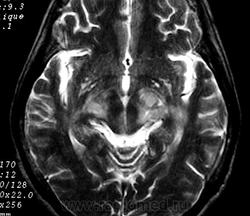

ГМ. Рассеянный склероз 2. +

Рассеянный склероз